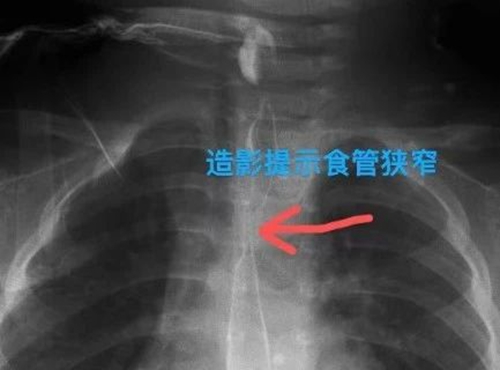

針對(duì)萌萌的病情,救治團(tuán)隊(duì)進(jìn)行對(duì)癥治療,患兒病情終于穩(wěn)定下來。但團(tuán)隊(duì)成員絲毫不敢大意,叮囑萌萌父母定期復(fù)查,及時(shí)評(píng)估食管恢復(fù)情況,并做好食管狹窄的治療預(yù)案。1個(gè)月后,萌萌復(fù)查結(jié)果提示食管出現(xiàn)明顯的狹窄,狹窄段長(zhǎng)約2cm,最窄處僅有3mm。

兒童消化內(nèi)科、胸外科團(tuán)隊(duì)協(xié)手,在胃鏡下成功完成食管球囊擴(kuò)張術(shù)。所幸治療及時(shí),術(shù)后,萌萌食管狹窄恢復(fù)良好,已可以經(jīng)口進(jìn)食。